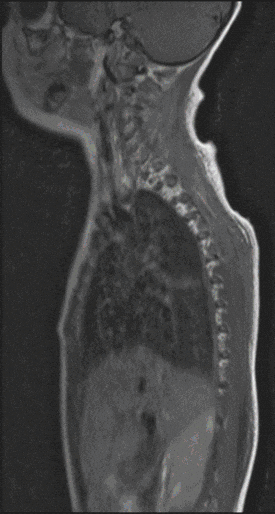

In most cases, the tumors of the spinal cord are histologically similar to the tumors of the brain. However, the treatment strategy differs significantly from operations on the brain. Tumors can arise outside the spinal cord and compress it massively, or they arise inside the spinal cord and can drive it up from the inside. Both pose a threat to function with the consequence of spinal cord syndromes (e.g. paraplegia).